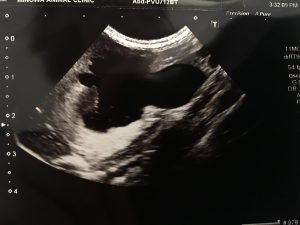

尿管結石の摘出手術